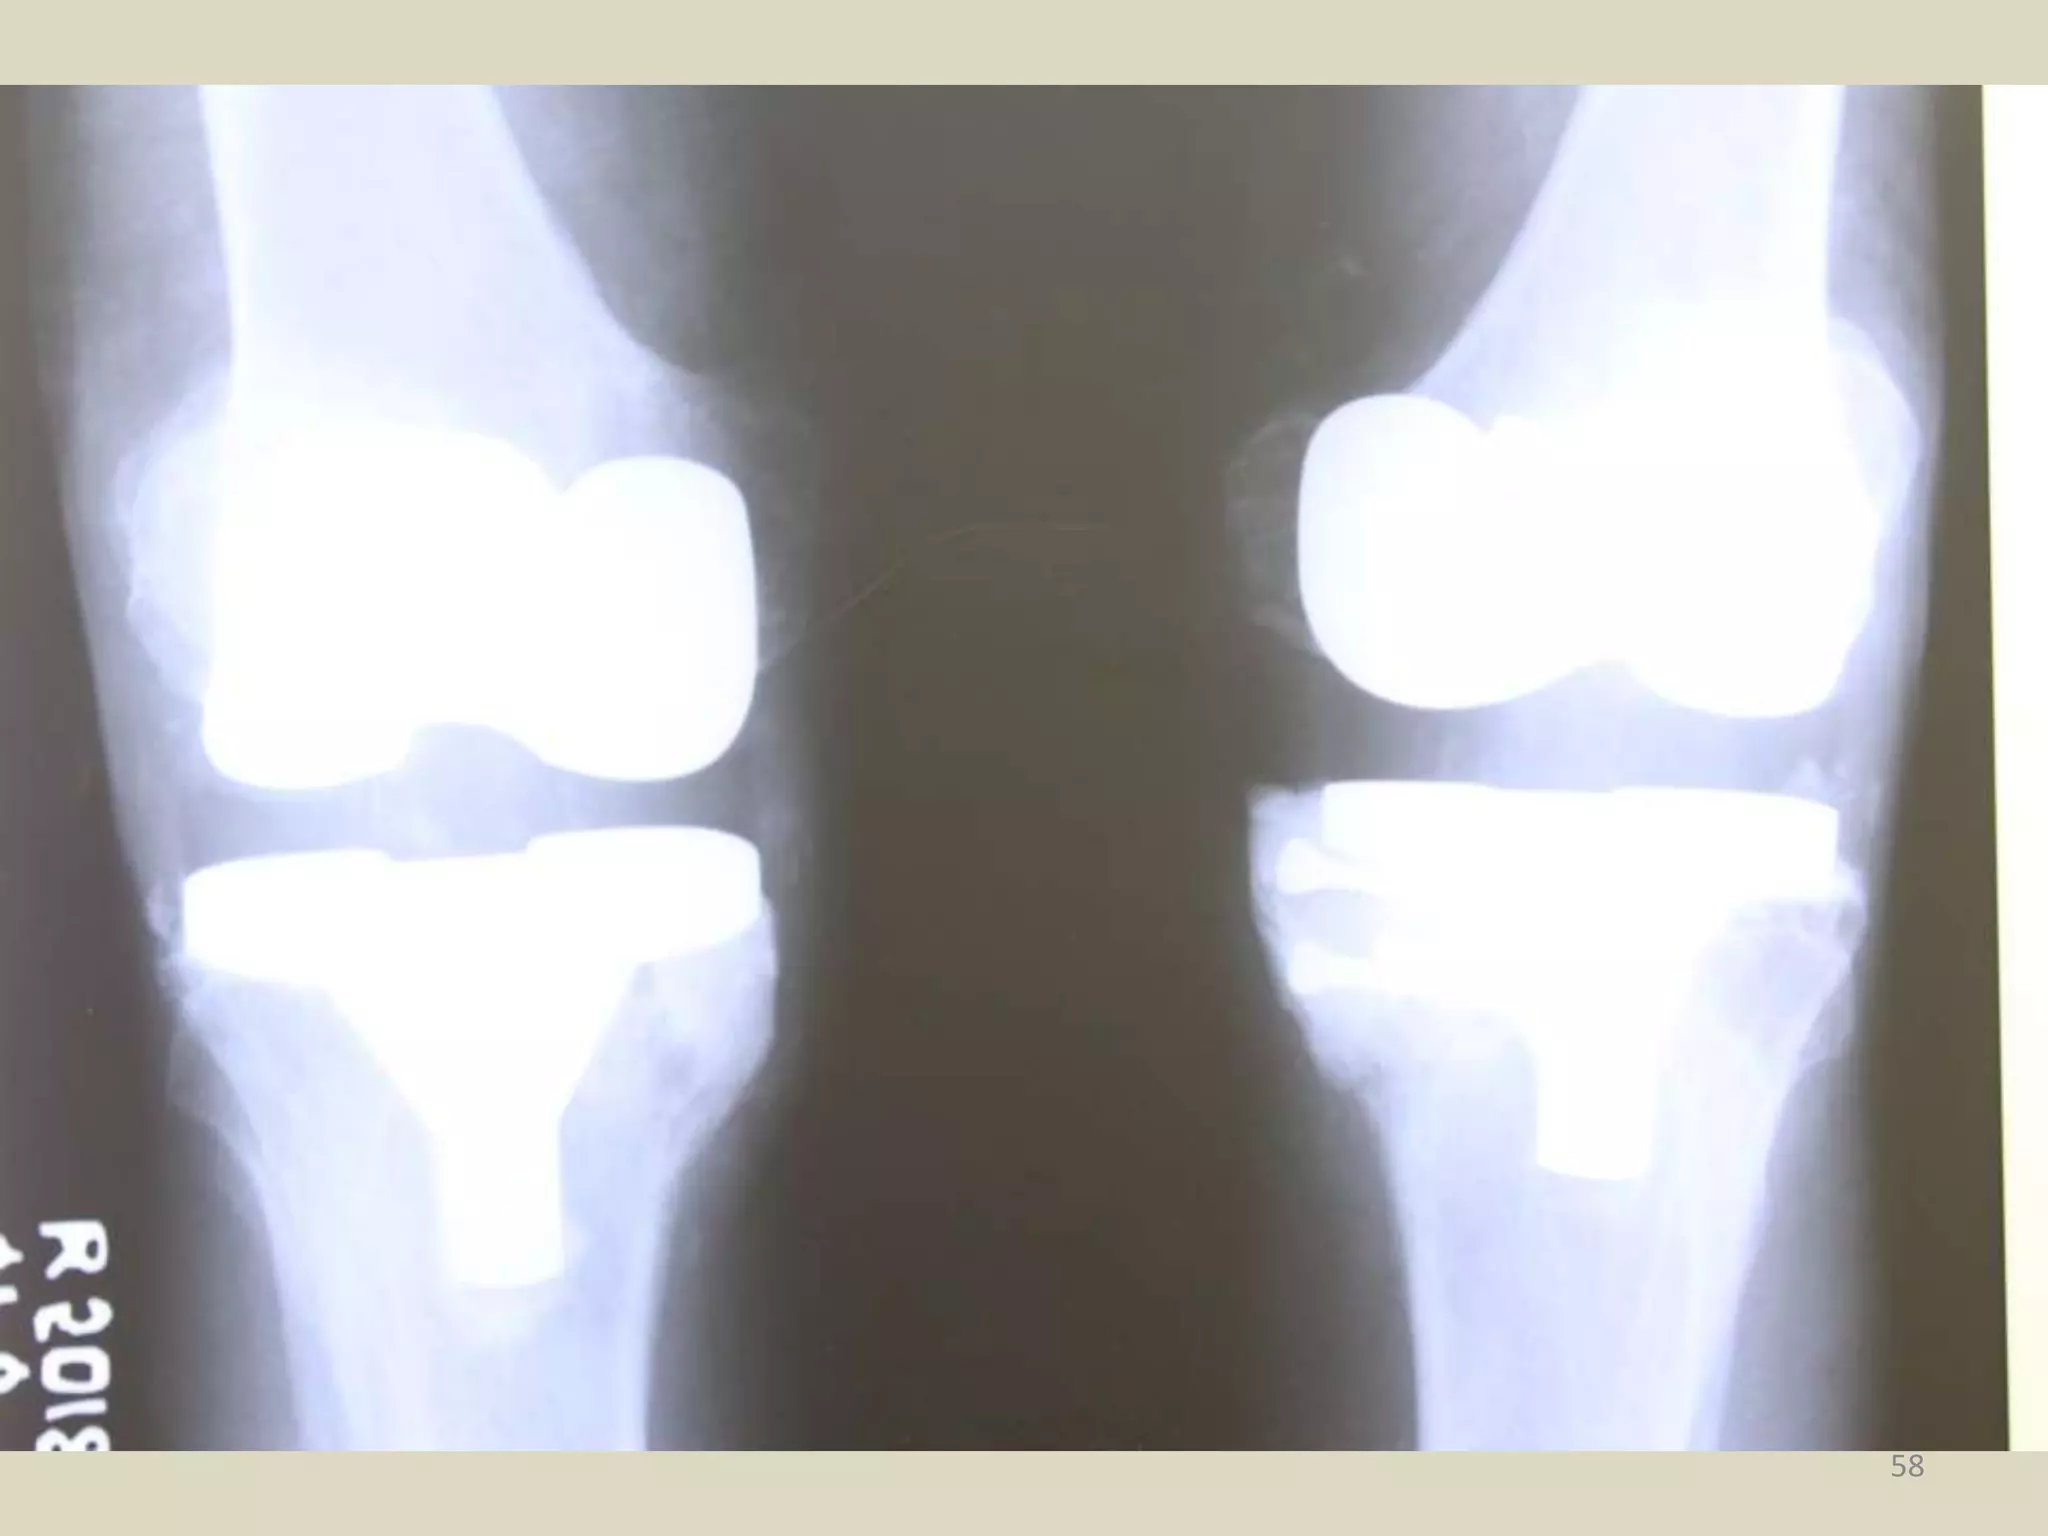

58

• #59 Post TKR Both Knees Status.